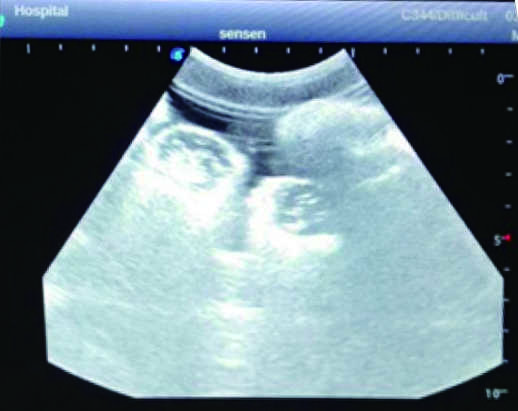

This model is an ideal choice for ultrasound-guided femoral arteriovenous puncture & abdominocentesis training with true-to-life skin feel and touch, accurate anatomical structures and real clinical ultrasound images. Realistic resistance to needle tips and correct landmarks provide excellent hands-on experience.

2)  Real clinical ultrasound images with clear anatomical structures like intestines, part of the liver, arteries and veins, etc.